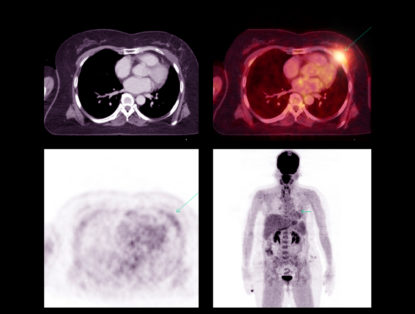

Posted on May 13, 2022

PET CT Scans (also known as PET Scans) have been used for medical diagnosis since the 1970s. The technique has been continuously refined since then ...

Read More